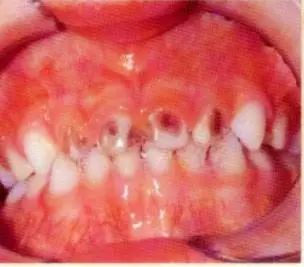

然后就变成这样了。

别质疑一小点蛀牙到一大片蛀牙的发展,

牙齿又不是荷花,

怎么能做到出淤泥而不染呢?

传染是分分钟的事情。